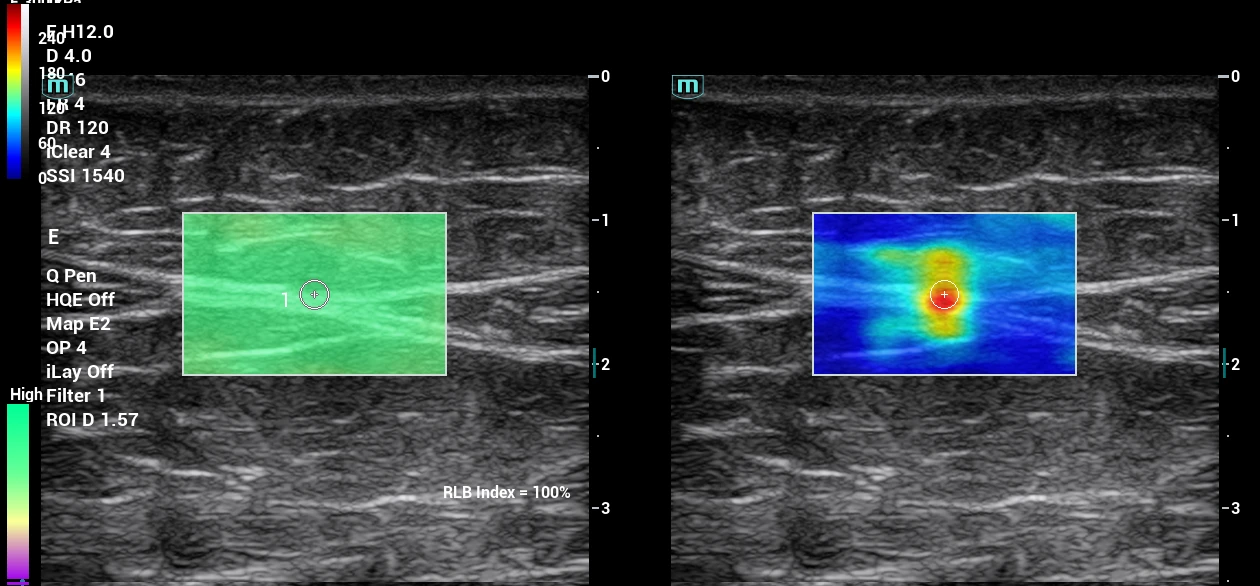

Jednou z najpodstatnejších je inovácia v diagnostických postupoch pri vyšetrení a ošetrení svalových štruktúr v oblasti celého tela, panvy a svalov panvového dna. Objektivizáciou funkcie svalov panvového dna a vybraných svalov trupu prostredníctvom 2D a 3D/4D ultrazvukového vyšetrenia získame komplexnejší pohľad na problém a dokážeme efektívnejšie navrhnúť vhodnú liečbu.